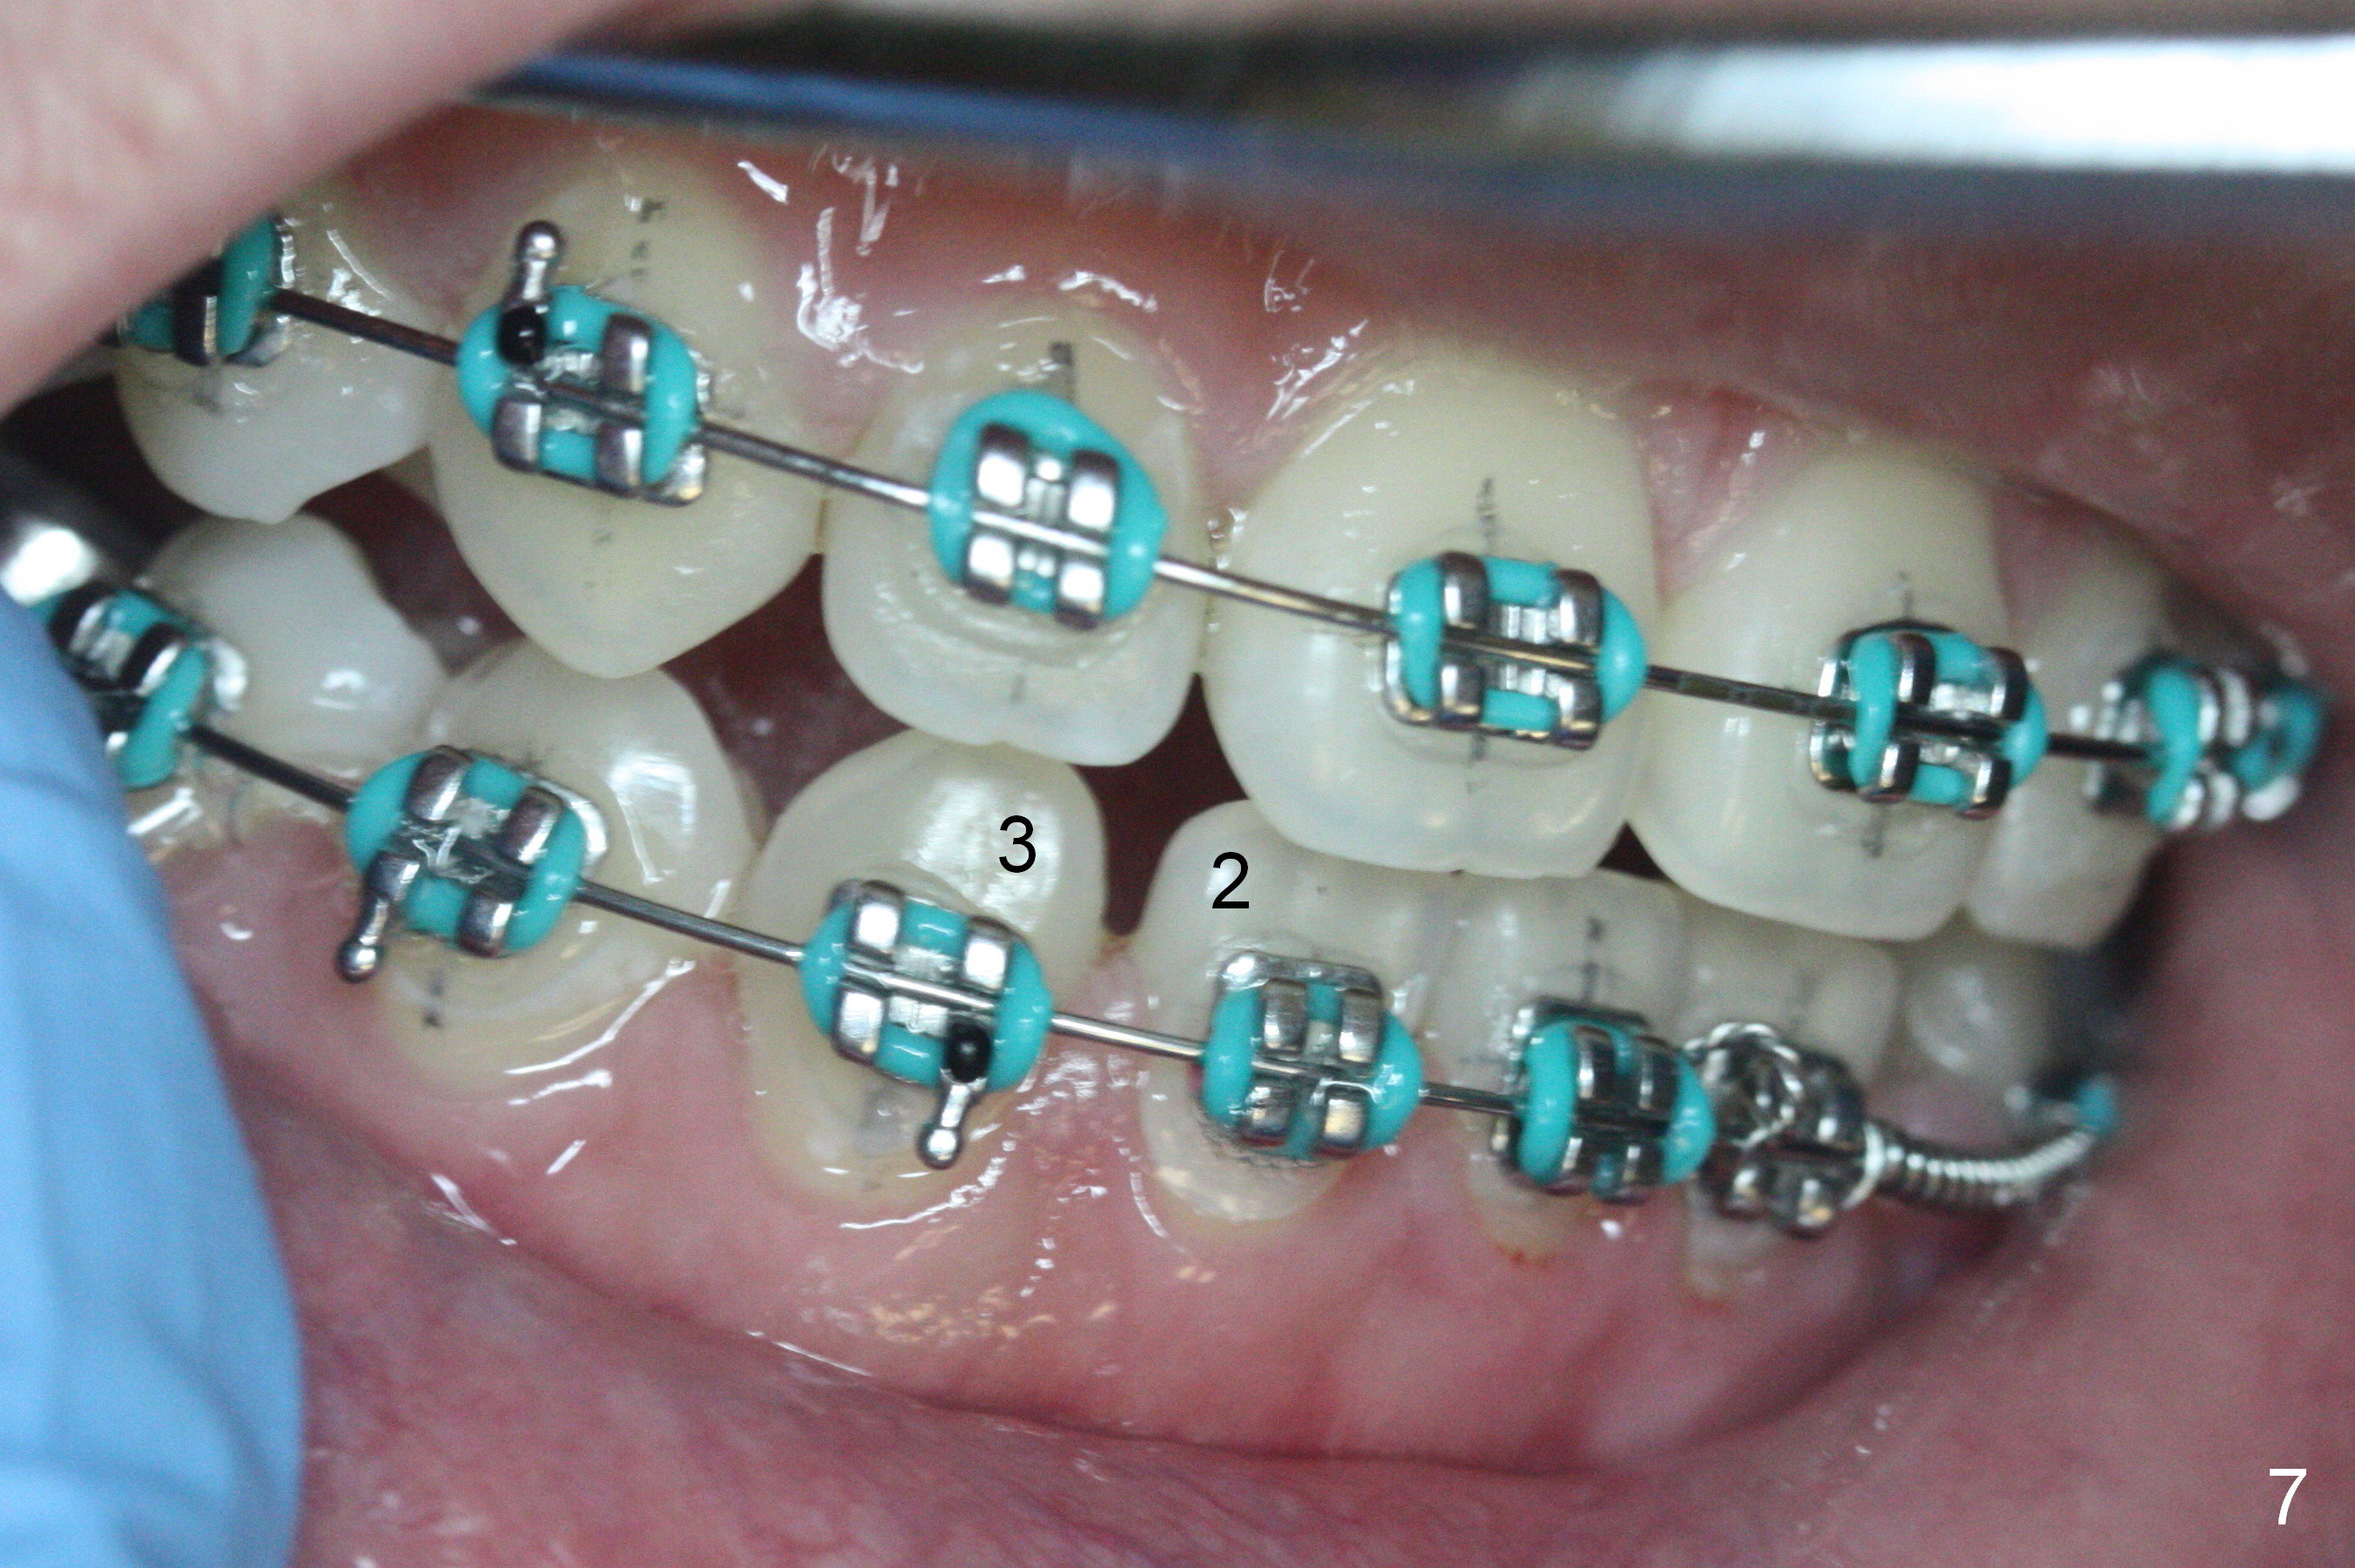

Diastema appears between LR2 and 3 (Fig.7) 2.5 months post banding, while open coil spring is placed between LL1 and 3 (Fig.8). Due to tension between LR 6 and 7 while insertion of 18 SS wire (saved), the lower 16 niti wire is reused whereas the upper wire is changed to 18 ss (Fig.7,8). Two rules are violated in this case. Stiffer wire (18 ss) should be used while placing open coil spring. Ligature wire has to be used to engage an open coil spring (Fig.8: 1). The advantage of using softer wire is easy engagement to LL2 bracket when the space is created. Using alastik in LL3 is convenient. In the next few appointemtns, we will detect any adverse effects of rule violation. In fact alastik holds the wire in place without any ill effect.